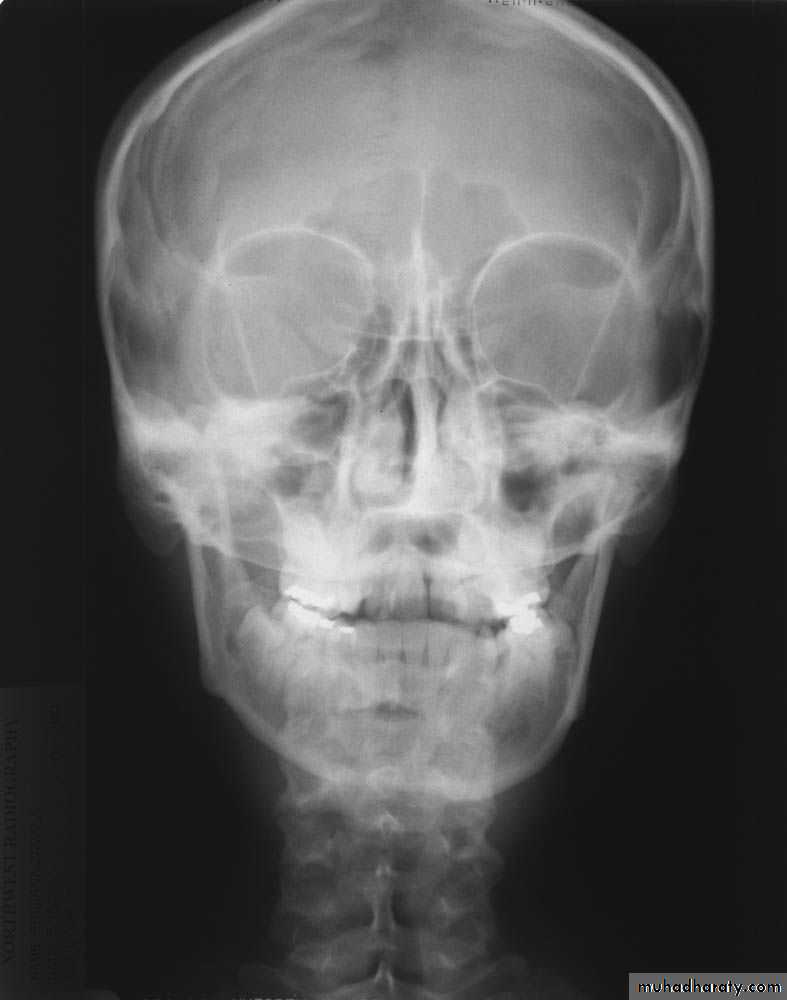

Skull X-rayBony configuration and shape

Bone densityAny Lytic lesion

Any fracture

Any calcification

Diploë, pituitary fossa, paranasal sinuses, orbits

The sutures